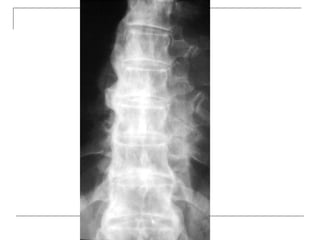

 Lateral

-fracture/wedging

-kyphosis

-spondylolisthesis

Plain x-rays